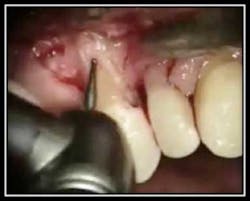

The below pictures define an area of root resorption that clinically and radiographically exhibited pocketing and bone loss. The attached video link shows a microsurgical repair of root resorption with Geristore; a radiopaque, hybrid ionomer composite used for subgingival restorations.

Geristore repair

By Dr. John Y. Kwan The below photos and corresponding video link show a root resorption and Geristore repair of #25 lingual.

A probe defines the resorption

Retention grooves being placed for Geristore placement